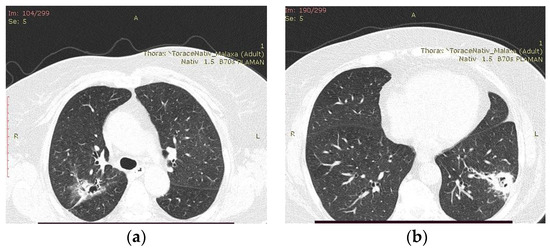

2.2. Blood Workup, Functional Tests, Bronchoscopy, and Radiological Findings

2.3. Treatment and Monitoring